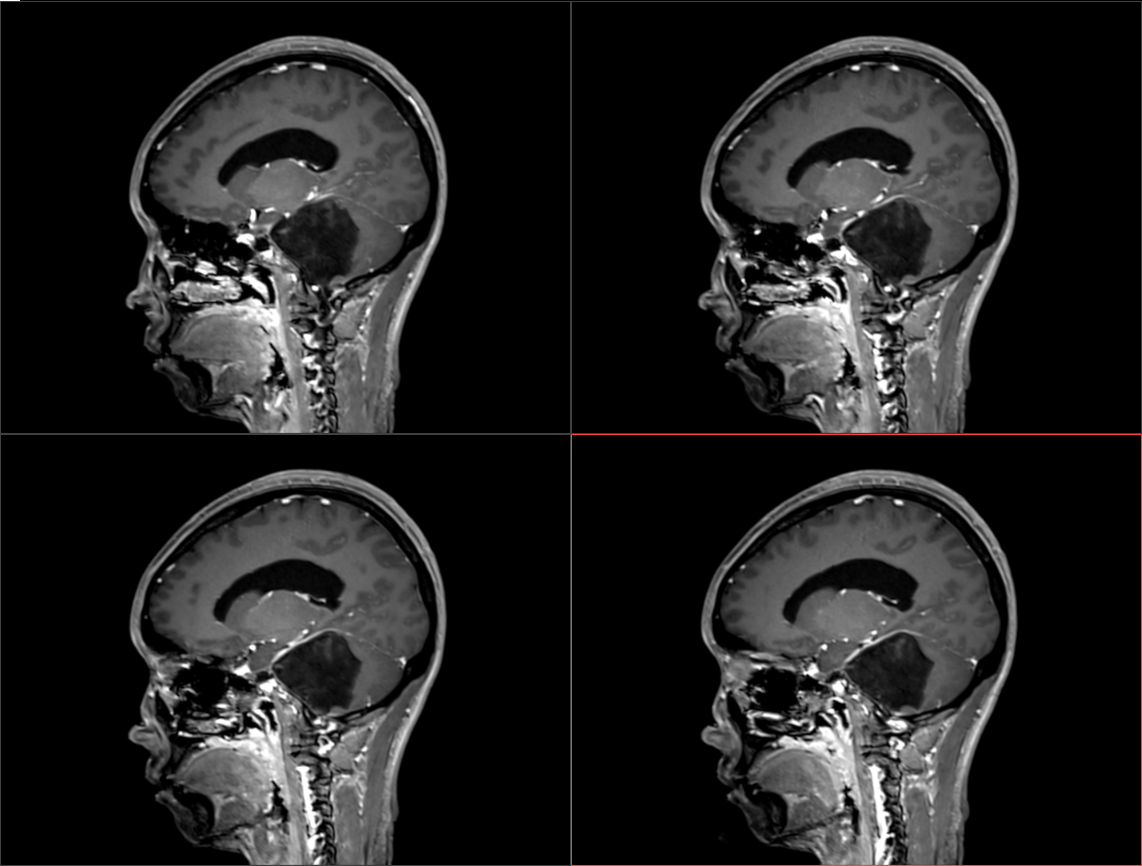

患者于入院前半年无明显诱因出现头痛、头晕,较剧烈,可耐受,无恶心、呕吐,无意识丧失,口服“止痛药(具体药名、剂量不详)”后症状稍缓解,入院前1周上述症状较前加重,患者前往当地医院就诊,行头颅MR示:1.左侧桥小脑角区占位,结合平扫及增强,现多考虑:皮样或表皮样囊肿。2。幕上梗阻性脑积水、脑室轻度积水。3.右侧上颌炎。现转至我院就诊。

术前影像: